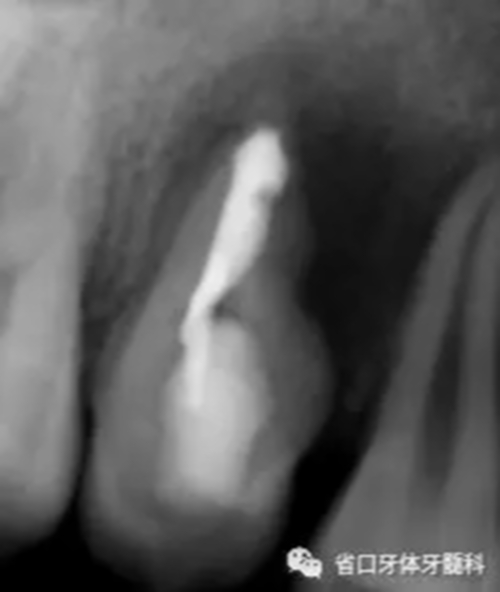

圖4 試尖